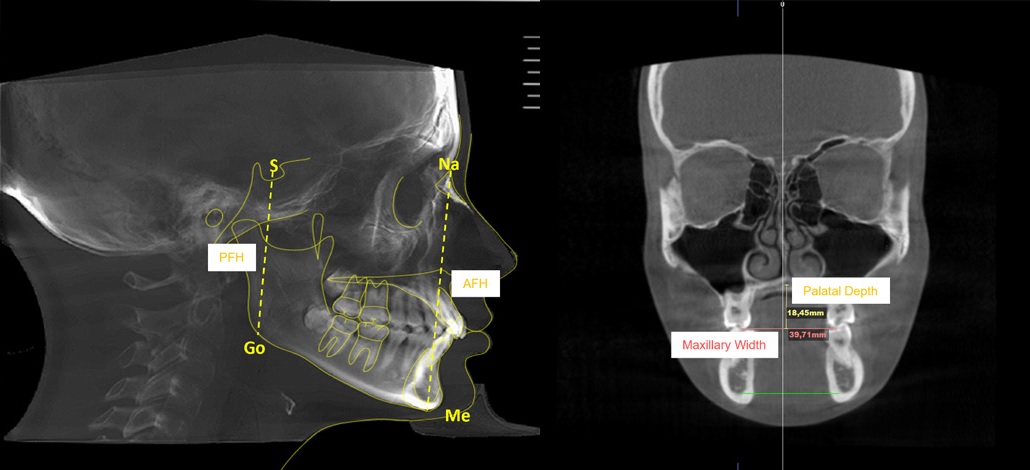

Orthodontic tracing was performed in the mid-sagittal plane slice using the same software. Cephalometric tracing assessed the following variables: anterior facial height (Na-Me), posterior facial height (S-Go), maxillary width, and palatal depth (Figure 1).

The limits of the nasopharynx and the oropharynx were determined for the upper airway assessment. The following landmarks were identified as the nasopharynx boundaries: (1) posterior nasal spine, (2) sella, and (3) the odontoid process tip, forming a triangle (Figure 2a). For the oropharynx, four anatomic points were identified: (1) posterior nasal spine, (2) epiglottis tip, (3) odontoid process tip, and (4) posterior superior border of the fourth cervical vertebra (Figure 2b). Afterward, the software calculated the corresponding volume in cubic centimeters (cm3) and the minimal sectional area in square millimeters (mm2). The sum of both nasopharynx and oropharynx volumes represented the total upper airway volume.